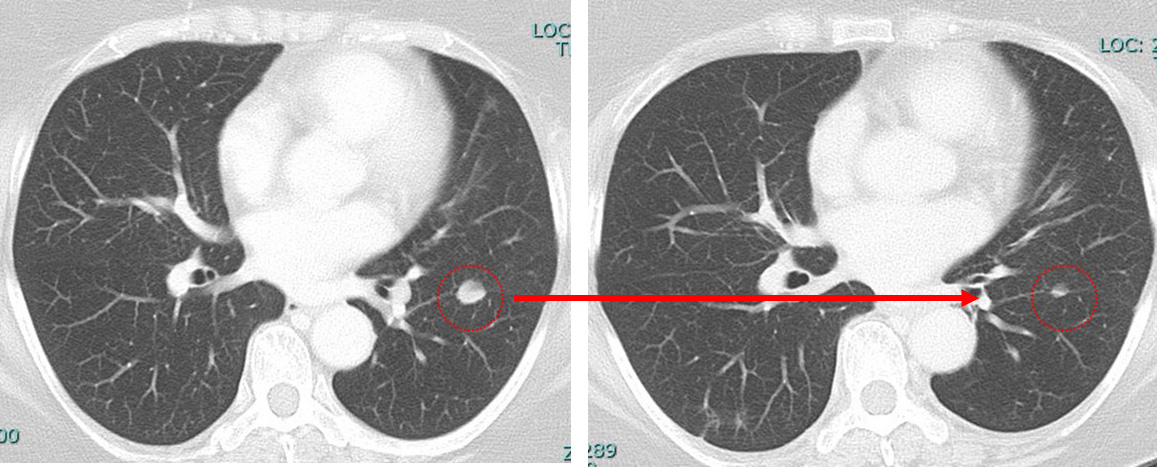

肺 かなり効いている

肺転移は(分子標的薬だけで)コントロールされている。

①「多発肺転移」は画像上かなり小さくなっているのに「胸の腫瘍は小さくならない」

少数臓器のオリゴ転移(oligometastatic disease:OMD)に対しては転移巣を切除することで臨床成績の改善が得られる可能性が論じられるようになってきた。

遠隔転移があるから手術は無意味、一生治らない。どうせ治らないから楽な治療でいいよ(と、抗がん剤もされずに)2年半頑張ってきた12566さん。

その2年半で得られた、「肺病変は小さくなったよ」という言葉

「肺病変が小さくなっている」のだから、この「いつまでも自分は癌だ」と打ちのめされてしまうこの(胸にある)腫瘍を何故手術してはいけないのか??

anthracyclin終了時の時点でのCTでcCR

病変が(少なくとも)画像上消失した状態。

「癌から解放されたのでは?」と思える瞬間があるということ